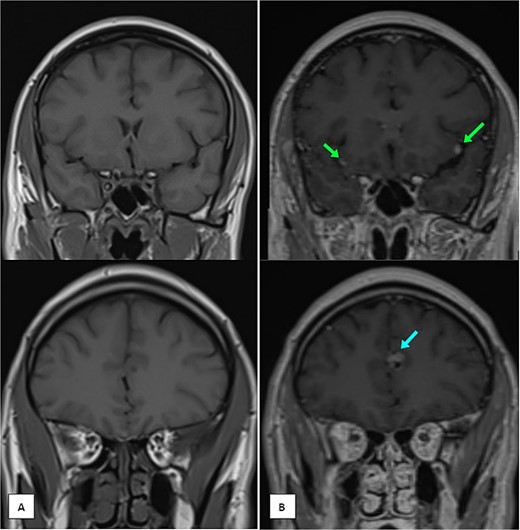

Months later, persistent back pain led to further imaging, which revealed progressive intradural lesions and new extra-axial meningeal nodular lesions likely representing meningeal deposits (Fig. 2). Despite the absence of recurrent nasopharyngeal mass, biopsy of the spinal lesions confirmed metastatic NPC (Fig. 3), indicating disease progression despite an initial excellent response to treatment.

MRI of the brain (A) coronal T1 pre-contrast and (B) coronal T1 post-contrast images showing multiple leptomeningeal enhancing nodules. The largest are seen at the left frontal parafalcine region (as shown in the single arrow) and bilateral sylvian fissures (as shown in the two arrows).